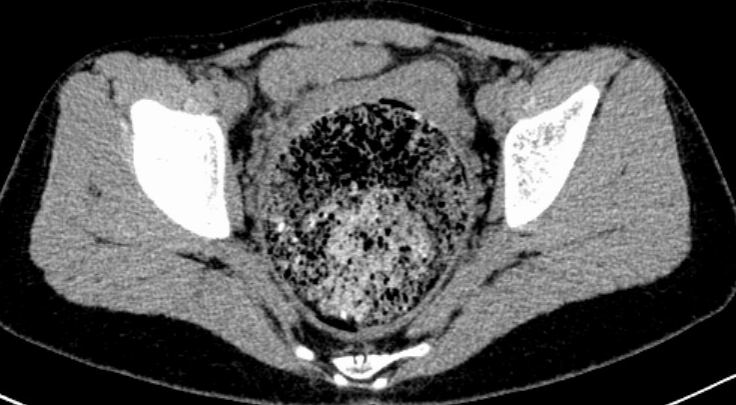

腹盆腔CT上显著扩张的直肠

在小娜的腹盆腔CT报告中,显示出明显的直肠扩展现象。这一异常表现引起了医生的重视。为此,王楠楠会同放射科、外科等专家对小娜进行了会诊,最终诊断其患有“脊髓栓系综合征”。